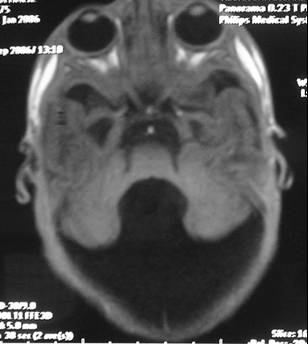

DWM arka çukur denen kafatası içinde beyincik, beyin sapı ve dördüncü karıncığın yer aldığı boşluğun doğumsal kusurudur. Beyinciğin vermis denen orta kısmı ya hiç gelişmemiştir ya da çok az bir kısmı gelişmiştir. Dördüncü karıncık genişleyip kistik bir hal almıştır (Resim 1). Bu kistik genişleme beyin omurilik sıvısının (BOS) dördüncü karıncığı terk ettiği deliklerin kapalı olmasına bağlanmaktadır. Bu hastaların %90’ında hidrosefali bulunmaktadır ve %75-80’inde doğumdan sonra ilk 3 ayda hidrosefali mevcuttur. DWM 25000-30000 canlı doğumda 1 görülmektedir.

Resim 1: (a ve b)Yatay MR görüntülerinde beyinciğin orta kısmının (vermis) gelişmemiş olduğu ve dördüncü karıncığın genişlemiş olduğu, (c) yan MR görüntüsünde kistik dördüncü karıncık izlenmektedir.